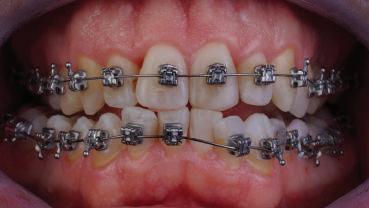

closed.

21Dental Tribune Bulgarian Edition / октомври 2022 г. ДИАГНОСТИЧНИ РЕЗУЛТАТИ: 1. Възраст на пациента: 21 години 2. Скелетен клас III (ANB 0) 3. Зъбен клас 3 4. Ръбцова захапка във фронта, кръстосана в дисталните участъци 5. Тясна горна челюст 6. Overjet – 0 мм, Overbite – 0 мм 7. Несъответствие на горната с долната средна линия 8. Единични контакти в ЦО 9. Хиподивергентен тип на растеж SN/MP – 33.5 10. Неравен гингивален контур 11. Неравна линия на усмивката 12. Тенденция за рецесии в долен фронт ПРЕПОРЪЧИТЕЛНО ЛЕЧЕНИЕ: Пълно ортодонтско лечение с метални брекети „Алекзандър“ Корекция на клас 3 захапката в областта на кучешките зъби с екстракция на първите пре молари в долна челюст Корекция на кръстосаната захапка в дистални участъци Коригиране на ръбцовата захапка във фронта Подобряване на ОJ и OB на пациента Стрипинг в долен фронт Подреждане на зъбите в горната и долната челюст Професионално хигиенизиране и профилактични дентални прегледи са препоръчителни на всеки 6 месеца. 1-ви месец След 1 месец са залепени брекети в горната челюст – поставена е еластична дъга. 016 NiTi. В долната челюст са елиминирани ротациите, поставена е стоманена дъга. 016SS, закалена с ток, и еластична верижка за затваряне на пространствата. 3-ти месец В долната челюст е поставена трета дъга – 17 x 25 NiTi с къси лигатури и верижка

В горната челюст се затварят пространствата с дъга .016SS и верижка. 5-и месец На 5-ия месец след залепяне на брекетите в долната челюст е поставена стоманена дъга 16 x 22 SS с четвъртито сечение, омега луп и тай бек. В горната челюст е поставена дъга 17 x 25 NiTi. Поради липсата на стабилни оклузални контакти са поставени лингвални верижки в областта на моларите, за да се предотврати нежелана ротация на 7-ите зъби. 6-и месец На 6-ия месец от началото на лечението са екстрахирани долните първи премолари, поставена е дъга 16 x 22 SS със затваряща чупка teardrop. Чупката се активира всеки месец по 1 мм с чинч-бек. клиничен случай | ортодонтия СТЪПКИ НА ЛЕЧЕНИЕТО Начало на лечението Лечението започва с поставяне на апарат за бърза експанзия в горната челюст. През първия месец от лечението са направени 24 оборота на апарата за експанзия. Залепени са брекети в долната челюст, поставена е дъга 17x25 CuNiTi, като са предпи сани клас 3 ластици (1/4”,4 1/2 oz) по време на сън, за да се осигури контрол върху торка на долните резци. Фиг. 2а Фиг. 3a Фиг. 4a Фиг. 3b Фиг. 4b Фиг. 3c Фиг. 4c Фиг. 3d Фиг. 4d Фиг. 3e Фиг. 4e Фиг. 5a Фиг. 5b Фиг. 5c Фиг. 5d Фиг. 5e Фиг. 6a Фиг. 6b Фиг. 6c Фиг. 6d Фиг. 6e Фиг. 7a Фиг. 7b Фиг. 7c Фиг. 7d Фиг. 7e Фиг. 2b Фиг. 2c Фиг. 2d

Dental Tribune Bulgarian Edition / октомври 2022 г.22 клиничен случай | ортодонтия 14-и месец В горната и долната челюст са поставени последни стоманени дъга с омега луп и тай бек – 17 x 25 SS с четвъртито сечение. Назначени е ластик за средната линия в комбинация с клас 3 ластик (1/4”, 6 1/2 oz). Контролни рентгенографии 13-и месец Екстракционните пространства са затворени. Направена е контролна панорамна снимка за оценка позицията на корените. Взето е решение за презалепване на брекетите на 12, 22 и пръстените на 36 и 46. 21-ви месец Средната линия в горната и долната челюст съвпадат. Ластиците са спрени. Свалени са пръстените и брекетите в горната и долната челюст, зигзаг ластици не са използвани поради благоприятните оклузални взаимоотношения. Фиг. 11j Ортопантомография в края на лечението. Фиг. 11k Телерентгенография след края на лечението. Фиг. 11l Анализ на телерентгенографията след лечението. Фиг. 11m Последователност на дъгите в горната и долната челюст Фиг. 11n Суперимпозиция на PreOp и PostOp ортопантомографии. 10-и месец Затварянето на пространствата е предвидимо и контролирано, без да се отварят пространства в зъбната дъга. Фиг. 8a Фиг. 8b Фиг. 8c Фиг. 8d Фиг. 8e Фиг. 10a Фиг. 10b Фиг. 10c Фиг. 10d Фиг. 10e Фиг. 9a Фиг. 9b Фиг. 9c Фиг. 9d Фиг. 9e Фиг. 9f Фиг. 11a Фиг. 11f Фиг. 11j Фиг. 11l Фиг. 11m Фиг. 11n Фиг. 11k Фиг. 11g Фиг. 11h Фиг. 11i Фиг. 11b Фиг. 11c Фиг. 11d Фиг. 11e

Dental Tribune Bulgarian Edition / октомври 2022 г. 23клиничен случай | ортодонтия реклама Лечението е продължило 21 месеца. Проведено е домашно избелване с индивидуални шини. За автора: Д-р Радой Димитров завършва с отличие Факултета по дентална медицина към МУ–София през 2015 г. В продължение на 5 години работи в няколко водещи практики в София, като през 2019 г. заедно със своята съпру га д-р Траяна Димитрова основават собствена практика в гр. Гоце Делчев –Dimitrovi Dental Care. Посещава редица курсове за повишаване на квалификаци ята, но най-сериозен тласък в развитието на ортодонтската си практика получава след завършването на комплексната ортодонтска програма, воде на от д-р Иван Горялов, базирана на дисциплината „Алекзандър“ – система с повече от 50 години опит в целия свят. Д-р Димитров е член на Българския изследователски клуб „Алекзандър“. Взе ма участие като гост-лектор в симпозиума с международно участие The Power of the Alexander Discipline, който се проведе на 14–15.05.2022 г. С д-р Ди митров можете да свържете на тел. +359885 252 025. Заключение Представеният случай е ярък пример за възможностите и красо тата на дисциплината „Алекзандър“ – приложен е утвърден под ход с ясни правила и са постигнати очакваните цели. Резулта тът ще бъде дългосрочно стабилен, тъй като са спазени всички правила, които се отнасят към максимално комфортната пози ция на зъбите в края на лечението. Постигнати са красива усмив ка и стабилна оклузия. ПОСТИГНАТИ РЕЗУЛТАТИ ОТ ЛЕЧЕНИЕТО 1. Коригирана ръбцова захапка 2. Коригирана клас 3 захапка в областта на ку чешките зъби 3. Коригирана кръстосана захапка в дисталните участъци 4. Коригиран овърджет и овърбайт 5. Разширена е горната зъбна дъга 6. Подредени зъби в горната и долната челюст 7. Постигната е стабилна захапка с множество контакти в ЦО 8. Драматично е подобрена дъвкателната функ ция 9. Подобрена е линията на усмивката ДРУГИ ПРОВЕДЕНИ ДЕНТАЛНИ ПРОЦЕДУРИ 1. Домашно избелване на зъбите 2. Екстракция на мъдреците Фиг. 12a Фиг. 12b Фиг. 12c Фиг. 12eФиг. 12d Фиг. 12f Фиг. 12g Информация за дати, цени и отстъпки www.bracescourses.com 0889 22 55 01 Практически курсове лектор д-р Иван Горялов Дисциплината „Алекзандър“ ПЪТЯТ КЪМ СУПЕРУСМИВКИТЕ 100% връщане на цялата сума, ако не сте удовлетворени след преминаване на Ниво 1 Директно и индиректно залепяне на брекети Анализ, диагноза и план на лечение Лечение на клас 2 дълбока захапка Екстракционно лечение Лечение на клас 3 отворена захапка НИВО 5НИВО 1 НИВО 2 НИВО 3 НИВО 4